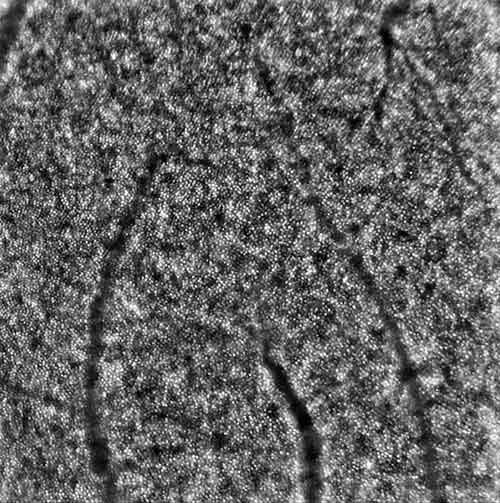

A technology called Adaptive Optics is able to eliminate ocular aberrations that distort and diminish retinal image quality, making it possible to visualize individual retinal cells of the photoreceptor layer in the retina. The ability to see retinal disease on a cell-by-cell basis allows a more precise study of the progression of disease or response to treatment, such as with drug toxicity, retinal degeneration, and macular hole and detachment repair.